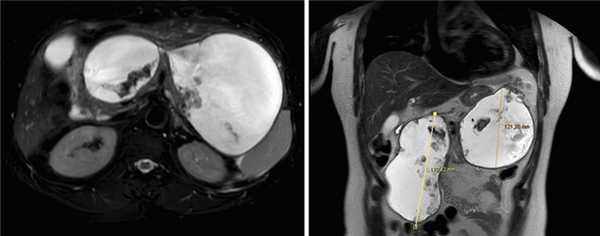

Рис. 1. Псевдокисты поджелудочной железы с секвестрами (магнитно-резонансная томограмма брюшной полости).

Для определения возможности эндоскопического дренирования гигантской псевдокисты пациенту была выполнена эндоскопическая ультрасонография, по данным которой в проекции головки-хвоста ПЖ определись два крупных жидкостных коллектора с ровными четкими контурами размерами 170×130 и 120×180 мм. Оба жидкостных скопления имели четкие границы, были правильной овальной и округлой формы с гиперэхогенной капсулой толщиной до 3 мм и содержали значительное количество гиперэхогенного содержимого с неровными контурами — секвестры. ПЖ просматривалась фрагментарно, контуры ее четкие и неровные, структура диффузно неоднородная, сниженной эхогенности, панкреатический проток в доступных участках не визуализировался (рис. 3).